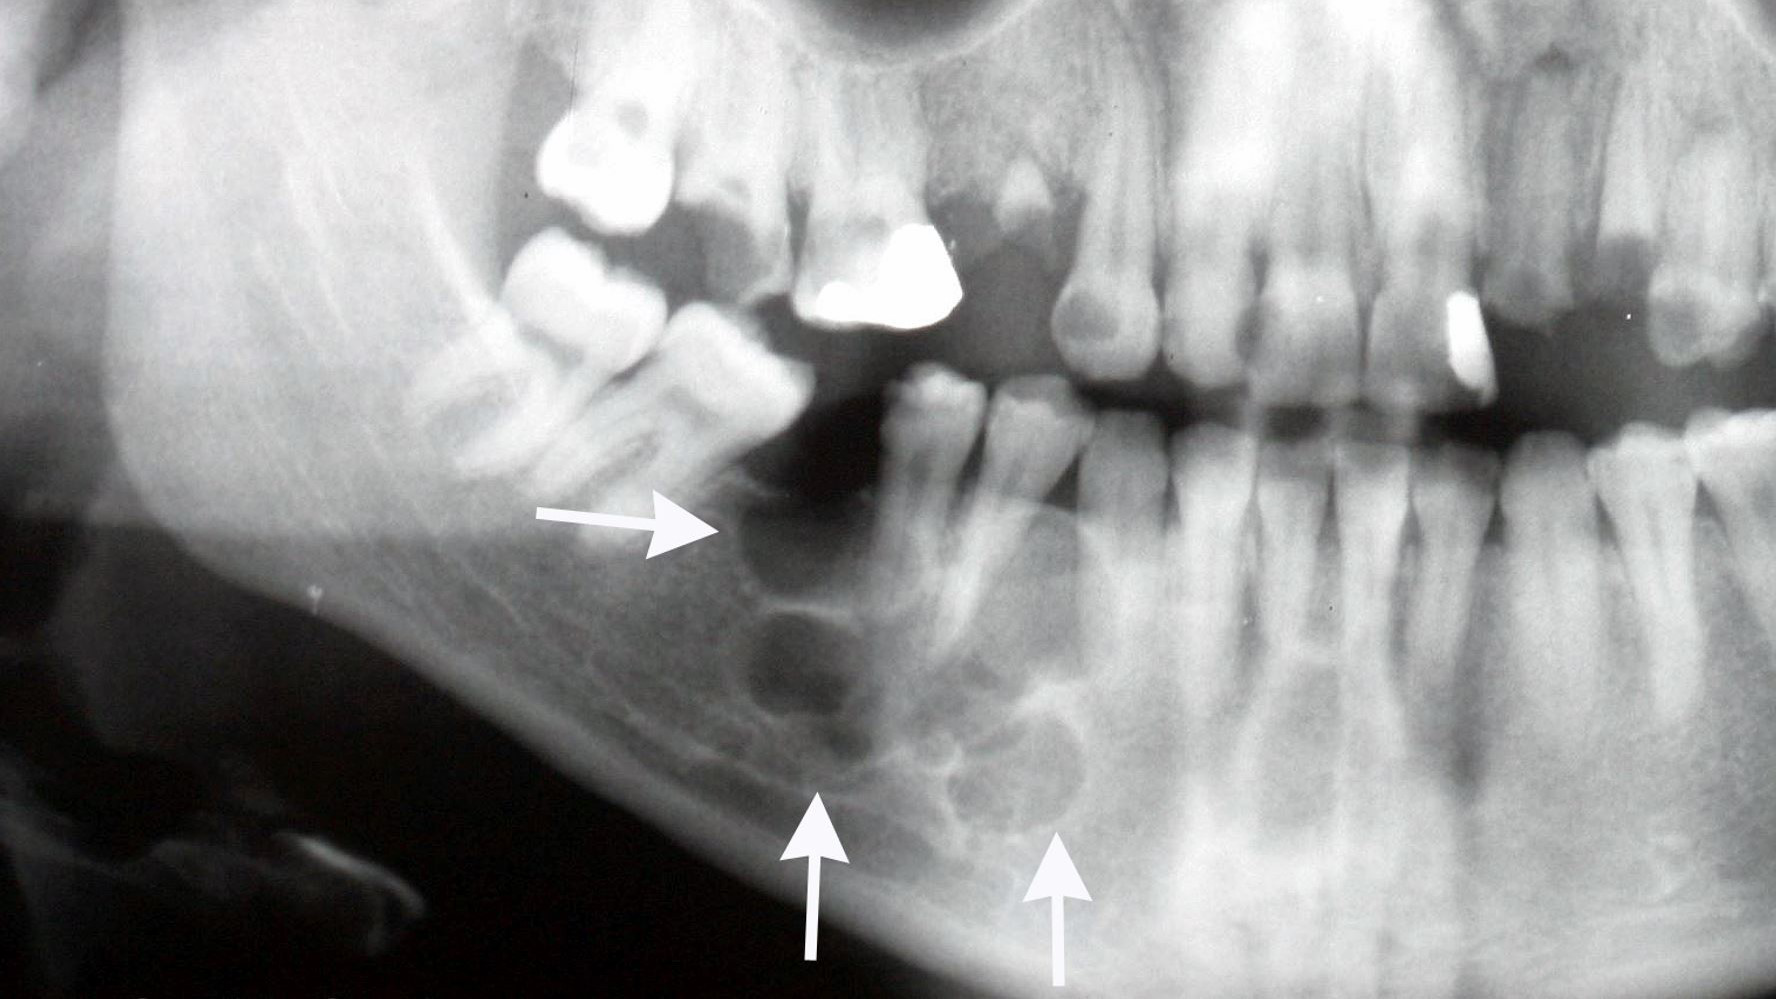

U men xương hàm thường không có triệu chứng cho đến khi bạn thấy sưng tấy trong miệng hoặc ở mặt. Nha sĩ có thể phát hiện ra u men xương hàm tình cờ trên phim X-quang hàm khi bạn đi khám răng định kỳ. Hoặc khi bệnh tiến triển gây ra các triệu chứng. Một số xét nghiệm được chỉ định bổ sung giúp chẩn đoán gồm:

- X-quang hàm trên và hàm dưới: Giúp xác định vị trí chính xác, kích thước u và tình trạng lan rộng của chúng.

- Chụp cắt lớp vi tính (CT-scan): Là phương tiện phổ biến nhất dùng để chẩn đoán, hình ảnh bong bóng xà phòng, giãn nở xương và tiêu chân răng giúp bác sĩ nghĩ đến chẩn đoán u men xương hàm.